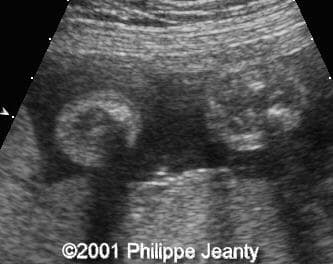

Note the striking cross-section of both lower legs with absence of the fibula on the right leg (left on the images):

clip0006

clip0007

and a longitudinal view of both lower legs:

image39

image38